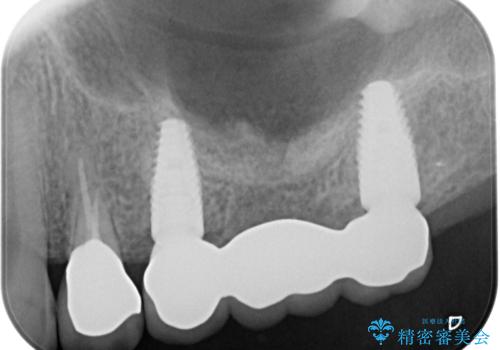

[ 重度歯周病 ] 骨造成・インプラント治療による咬合機能の回復

歯周病の精密検査の結果、たくさんの歯が残すことが難しい状態でしたが、歯周病治療で歯を残すことができることと、骨の造成を行えばインプラント治療も可能である、と判断し入れ歯ではなく、しっかりと噛めるような治療ゴールを目指し、治療を開始します。

歯周病治療を徹底的に行ったことで、残った歯の歯周ポケットはなくなり、奥歯のインプラントがあることでしっかりとかめるような咬合関係が確立されました。